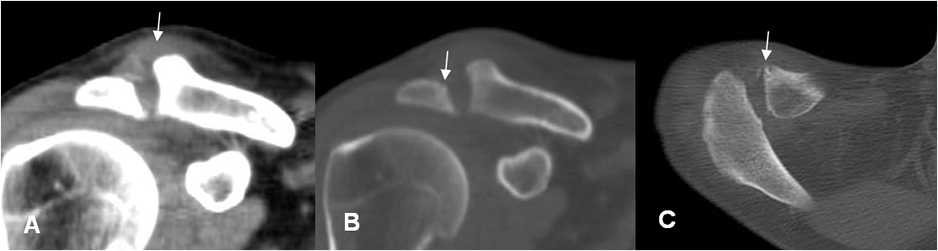

En la fase aguda la Rx simple puede ser normal. También puede existir edema de tejidos blandos y derrame articular. En niños el estudio comparativo es de mucha utilidad. (16). (Fig 63 A, 63 B y 63 C).

A: TAC reconstrucción coronal. Aumento del espacio acromioclavicular, con prominencia en los tejidos blandos en la parte superior.

B: TAC reconstrucción coronal y C: TAC axial. Incipientes esrosiones óseas en la clavícula y el acromión, por artritis infecciosa.